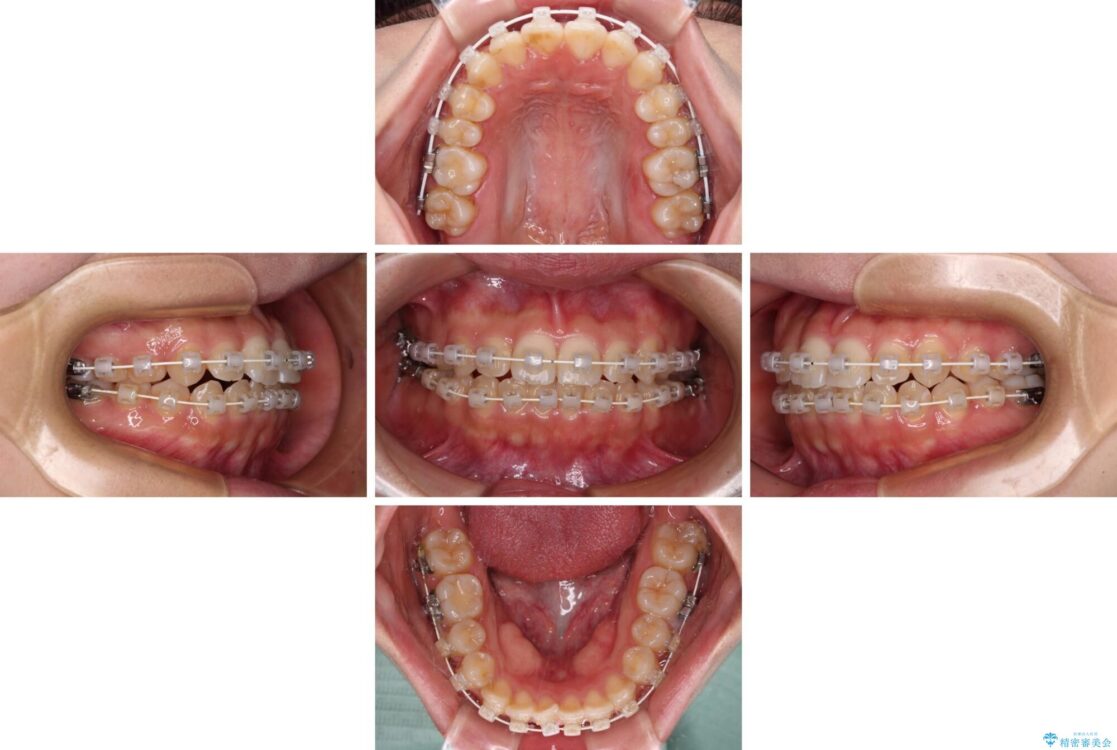

治療途中

• 【モニター】短期間で終わりたい ワイヤー装置での非抜歯矯正 治療途中画像

マウスピース矯正のような自己管理の煩わしさは避け、早く治療を終えたいとのことで、ワイヤー装置による矯正治療を行うこととしました。

当初予定通り、1年で治療を終えることができました。

後戻り防止はマウスピースで行うため、急に自己管理が必要となるため、移動の最後をマウスピース矯正で行うことで、マウスピース非装着による後戻りリスクを回避する工夫をしています。